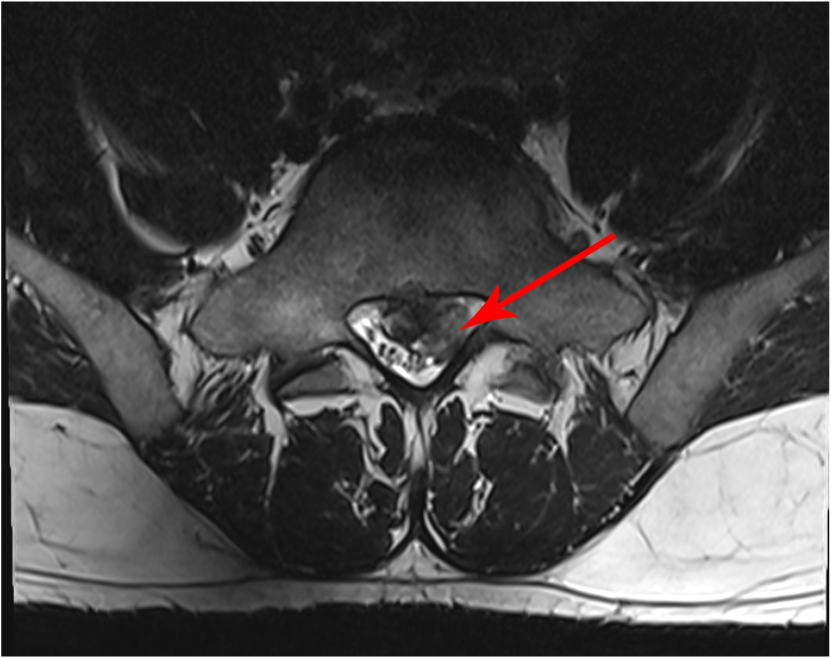

Die MRT-Bilder zeigen einen 27 jähriger Patienten mit plötzlichen Rückenschmerzen mit Ausstrahlung ins linke Bein, über die Wade bis in die äußeren Zehen. Vor allem im Fuss besteht ein Taubheitsgefühl.

In der neurologischen Untersuchung zeigte sich keine Schwäche der Muskulatur, dafür eine Abschwächung des Reflexes an der Ferse und die Taubheit.

Insgesamt kein Grund für eine Operation.

Der Patient wurde konservativ mittels Spritzen, Tabletten und Physiotherapie behandelt.

Das zweite und dritte Bild wurde nach 3 Monaten angefertigt.

Hier zeigt sich der hellgraue Anteil des Bandscheibenvorfalls vollständig resorbiert. Beinschmerzen sind zu diesem Zeitpunkt keine mehr vorhanden. Das Taubheitsgefühl hat sich deutlich verbessert und ist nur noch am kleinen Zeh vorhanden.